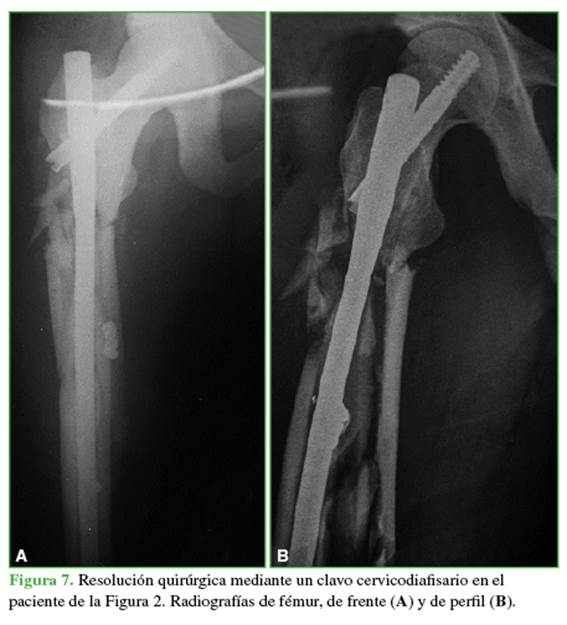

Los métodos de fijación utilizados se distribuyeron de la siguiente forma: 19 (54,29%) con clavo endomedular (Figuras 6 y 7) y siete (20%) que comprometían a la zona III con placas anatómicas bloqueadas.

En nuestra serie, había tres fracturas del fémur proximal, dos de ellas eran incompletas, solo una fue tratada mediante estabilización profiláctica con clavo cefalomedular. El otro paciente fue tratado con reposo y descarga de peso por 45 días; en este caso, la demora en la disponibilidad del material quirúrgico representó una limitación para la elección del tratamiento. El fundamento para el tratamiento quirúrgico en estos pacientes consiste en realizar un procedimiento simple y permitir la carga de peso inmediata y prevenir un procedimiento futuro complejo en caso de colapso o desplazamiento de la fractura.